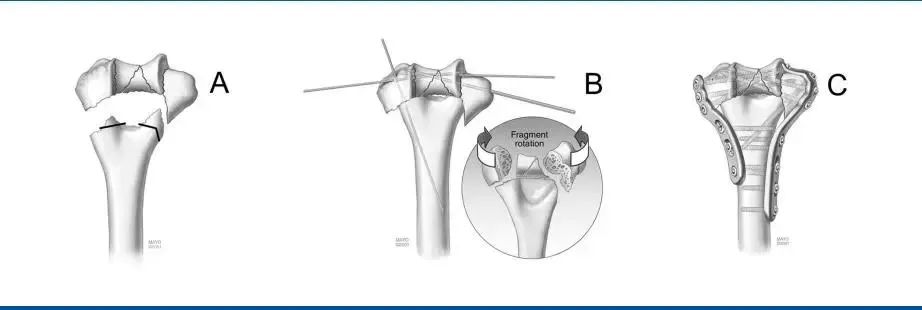

第一步:关节复位术。在轴面上倾向于相互旋转的关节碎片予以解剖复位,并暂时用克氏针固定。重要的是,克氏针应靠近软骨下水平,以避免干扰以后的螺钉放置,并远离钢板放置在外侧柱和内侧柱上的位置。一个或两个适当放置的克氏针可用于暂时固定与骨干对齐的远端骨折。

第二步:钢板敷贴和临时固定。将内侧和外侧预成型钢板放置并固定在肱骨远端,同时通过每个钢板的2号孔(从远端到近端编号)、上髁和远端骨块插入一个光滑的2mm或2.5 mm科氏针,以维持钢板与远端骨折的临时固定。

在每个钢板的开槽孔(5号孔)中放置一个螺丝钉,但没有完全拧紧,在压缩过程中为钢板留出了一些向近端移动的自由。由于每个接骨板的下表面在干骺端和骨干端都是管状的,所以只需稍微拧紧开槽孔中的螺钉,就可以提供良好的整个肱骨远端的临时固定。

第三步:关节固定。螺钉穿过外侧板的1号孔,从外侧向内侧穿过远端关节骨块,并被拧紧。在内侧使用3号孔重复这一步骤。

在年轻患者中,使用3.5 mm的皮质螺钉(以防止骨折),而在骨质疏松患者中,使用2.7 mm长的螺钉。远端的螺钉应该尽可能长,应该穿过尽可能多的骨折块。

第四步A:髁上加压。使用大复位钳在肱骨上水平提供横跨骨折的碎块间加压,首先固定外侧柱。在外侧板的4号孔中以动态压缩模式(插图)放置一颗螺钉。将其收紧可进一步加强在髁上水平的碎块间压加压(箭头),从而在内侧髁上脊引起一定程度的牵张(箭头)。

第五步:最终固定。克氏针都被移除,其余的螺钉被插入。远端螺钉交错打入,最大限度地固定在远端关节碎片。